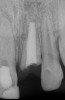

After that the patient was seen in the endodontic office periodically to monitor the retained roots and associated alveolar ridge. The root of No. 8 was retained for 8 years after fracturing, and the root of No. 9 was retained for 9 years. During that time there were no clinical signs or symptoms, nor were there radiographic signs of periradicular breakdown. A final endodontic check at age 19 found the coronal surface of the root of No. 9 had been exposed. The vertical level and horizontal width of the alveolar ridge appeared very similar relative to the adjacent teeth as it had been at ages 10 and 15 (Figure 8 and Figure 9). No evidence of periradicular breakdown appeared radiographically (Figure 10). The patient's growth was deemed nearly completed and he was referred to an oral surgeon for evaluation and placement of implants.

Fig 8. Age 19. Facial view of the ridge.

Figure 8